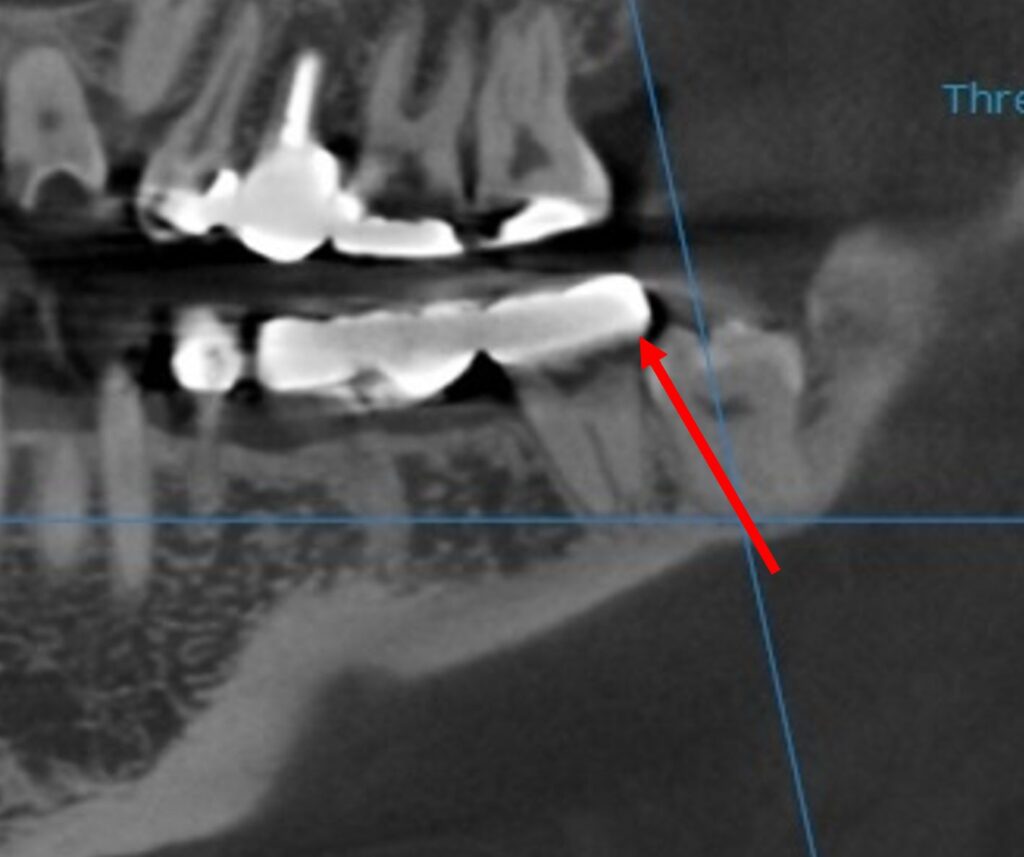

매교역치과 바른본에서 더 정확한 검사를 위해

촬영한 CT 사진입니다.

사랑니가 빨강색 화살표 방향으로 맹출을 하고 있고

이 방향이 앞쪽 어금니를 누르고 있는 것 같습니다.

환자분 연세가 사랑니 뿌리는 전부 자랐을 시기라

더 정확하게는

매복된 사랑니 주변 염증이

앞쪽 어금니를 압박하고 있다고 봐야 할 것 같네요.

아무래도 매복사랑니가

원인모를 치통의 이유인 것 같습니다.